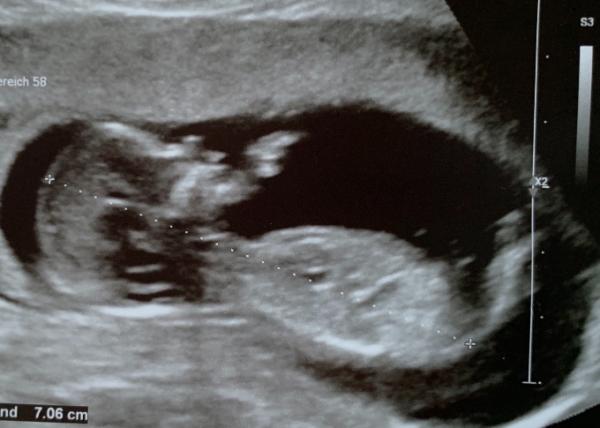

Antwort auf Beitrag von Würmchen032020

Bild 2 Vielleicht kennt sich jemand aus... ich leider garnicht.